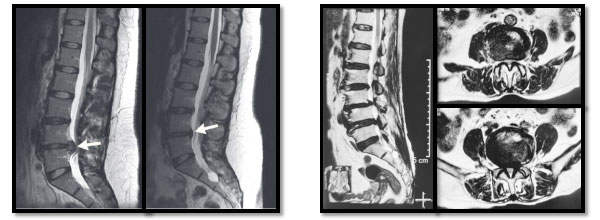

腰椎间盘突出                                      腰椎椎管狭窄

jz202203-3.jpg

双通道内镜下手术